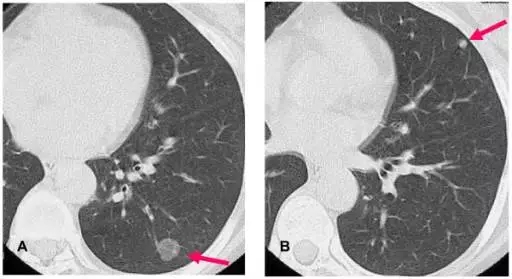

片来自Internet

一次肺部CT扫描产生200-300张片子,一个放射科医生全神贯注检查30个人的CT片子,需要150-180分钟。一家三甲医院平均每天接待200例左右的肺结节筛查患者,放射科医生每天至少需要读片4万张。这可以说是一种“劳役”般的工作,稍有疏忽,就会影响到诊断的准确率。

人工智能技术在医疗领域的应用,将极大地提高诊断的“准确率”,中国在肺癌诊断领域走在了世界前列,其突出优势表现在准确率达到90%以上,读片效率比人工读片提高5倍以上,基本上一分钟可以阅读一个病人的CT片。迅速读片出报告,可以大大减轻放射科医生读片劳苦,并且可以节省胶片等耗材的使用费用,如果广泛使用,可以缩小大小医院诊断水平的差距,让三、四线城市和乡村的病人享受到大医院的诊断水平。